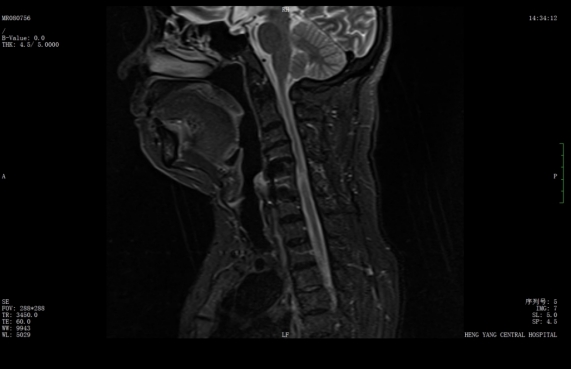

該患者此前因膽囊結石祁東縣人民醫(yī)院治療,來自衡陽市中心醫(yī)院駐該院副院長李攀峰為其主刀進行手術,術后患者恢復良好。后因突發(fā)四肢癱瘓、生活無法自理,為尋求進一步治療,經醫(yī)聯(lián)體通道轉入衡陽市中心醫(yī)院。脊柱外科錢軍博士團隊接診后,迅速組織詳細問診、體格檢查及系統(tǒng)術前評估。查體顯示患者四肢關鍵肌肌力僅I級,感覺功能明顯減退,結合影像學結果,診斷為頸脊髓損傷伴不全癱,有明確手術指征。

考慮到患者20年前曾有頸脊髓外傷史,并于外院行頸椎前路手術,此次手術區(qū)域存在嚴重瘢痕粘連,極大增加了手術難度與風險。錢軍博士團隊迅速啟動多學科會診,為患者制定個性化手術方案,最終決定施行頸椎后路手術,擴大椎管容積,徹底解除神經壓迫問題。

術前核磁共振提示:頸椎椎管狹窄、頸脊髓信號改變